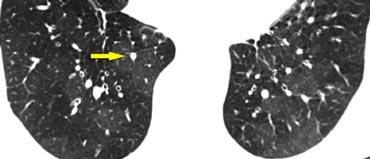

Dấu hiệu cành cây nảy chồi (Tree-in-Bud)

Trong bối cảnh các nốt trung tâm tiểu thùy, việc nhận diện dấu hiệu “cành cây nảy chồi” có giá trị trong việc thu hẹp chẩn đoán phân biệt.

Dấu hiệu cành cây nảy chồi mô tả cấu trúc phân nhánh không đều, thường dạng nốt, dễ quan sát nhất ở ngoại vi phổi.

Về mặt bệnh lý, nó đại diện cho các tiểu phế quản trung tâm tiểu thùy bị giãn và tắc nghẽn (chứa đầy chất nhầy hoặc mủ).

Sự hiện diện của dấu hiệu cành cây nảy chồi hầu như luôn luôn chỉ ra:

- Lan tràn nội phế quản của nhiễm trùng, chẳng hạn như lao (TB), phức hợp Mycobacterium avium (MAC), hoặc viêm phế quản phổi do vi khuẩn.

- Bệnh đường thở liên quan đến nhiễm trùng, bao gồm xơ nang và giãn phế quản.

- Ít gặp hơn, bệnh đường thở chủ yếu liên quan đến ứ đọng chất nhầy, chẳng hạn như bệnh phổi do nấm Aspergillus dị ứng phế quản (ABPA) và hen phế quản.

- Hít sặc.

Ví dụ minh họa

Trong hình ảnh bên trái, dấu hiệu cành cây nảy chồi được minh họa rõ ràng.

Trong bối cảnh lâm sàng phù hợp, dấu hiệu này cần gợi ý nghi ngờ lan tràn nội phế quản hoạt động của lao.

Đáng chú ý, ở hầu hết bệnh nhân lao hoạt động, HRCT thường cho thấy bằng chứng của lan tràn phế quản phổi ngay cả trước khi có xác nhận vi khuẩn học (6).